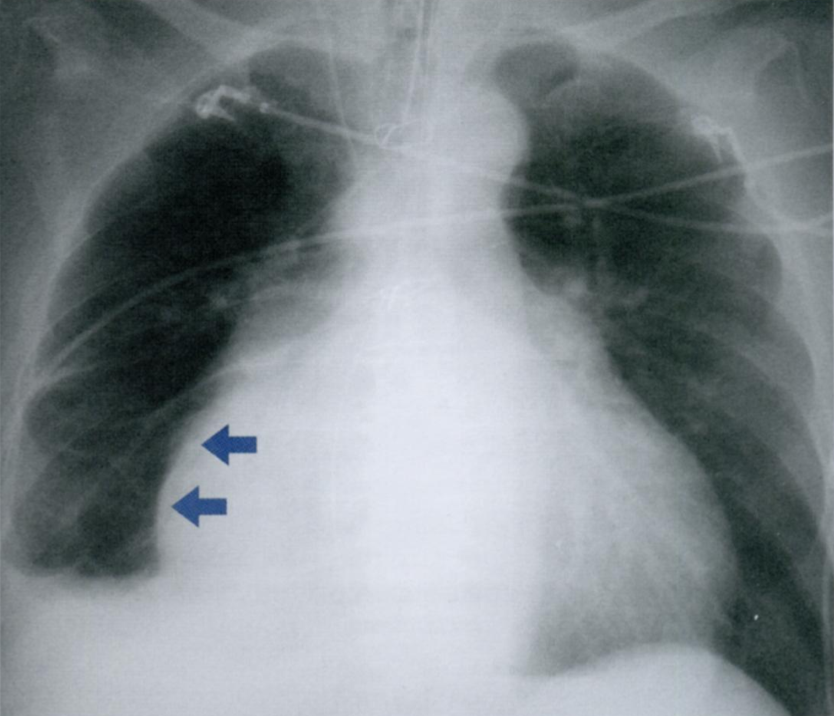

Относительно часто встречается трикуспидальная недостаточность, которая может развиваться, например, при митральном стенозе.

Клапан становится неполноценным из-за миогенной дилатации правого желудочка и кольца трехстворчатого клапана. Дилатация правого предсердия приводит к значительному расширению тени сердца вправо на рентенограмме в ЗПП (стрелки).